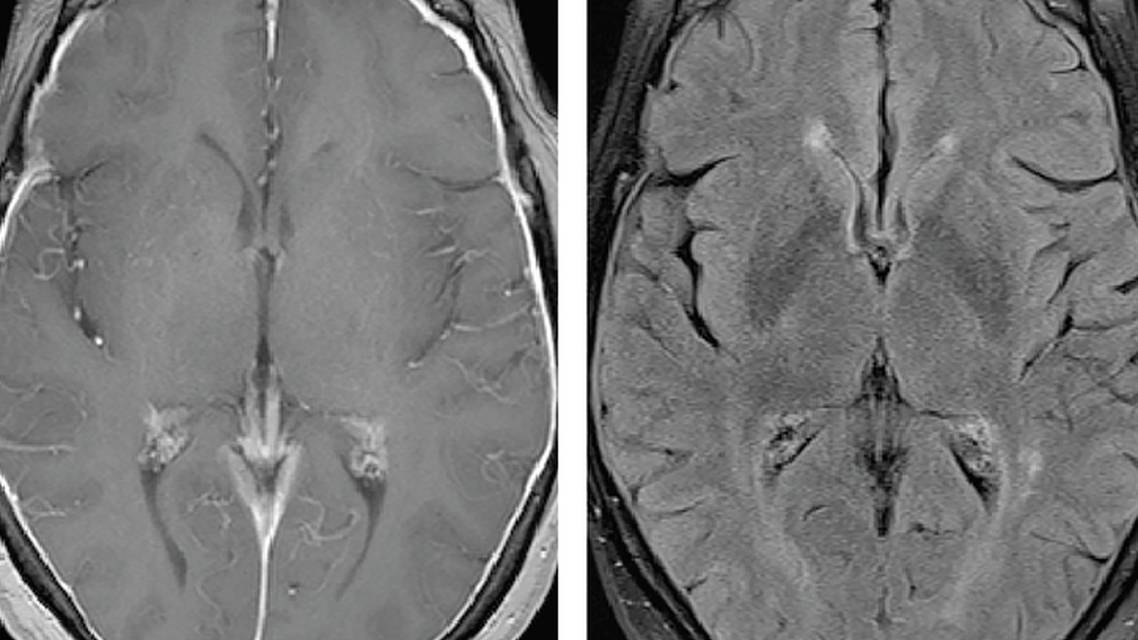

A repeat brain MRI, with and without contrast still showed diffuse dural and pachymeningeal thickening and enhancement throughout the supratentorial compartments (Figure). Based on the MRI findings with the differential to include pachymeningities, the decision was made to move forward with a lumbar puncture (LP) for cerebral spinal fluid (CSF) analysis and opening pressures. Difficulty was reported in obtaining CSF, and table tilting was required to collect enough fluid for testing. Mrs. A.'s opening pressure was 6 cm. She tolerated the procedure well and had no neurological complaints after the procedure. The analysis of CSF was negative for infectious, inflammatory, and neoplastic processes. The angiotensin-converting enzyme (ACE) level was slightly elevated with unknown significance. Serum ACE was normal. Based on the development of marked memory loss and subtle withdrawal from her hobbies, her CSF was also analyzed for AD biomarkers with findings of amyloid-β (Aβ)-42 of 341 pg per mL, phosphorylated tau 180.2 pg per mL with an Aβ to tau index (ATI) of 0.5, consistent with probable AD.

Figure. MRI imaging study with contrast. The axial image shows dural-pachymeningeal thickening and diffuse enhancement (A). The coronal image shows continued dural-pachymeningeal thickening and diffuse enhancement (B). The sagittal image shows noncontrasted view with typical age-related atrophy (C). The fluid attenuated inversion recovery (FLAIR) axial image shows scattered gliosis in the periventricular area probably representing chronic white matter disease bilaterally (D).